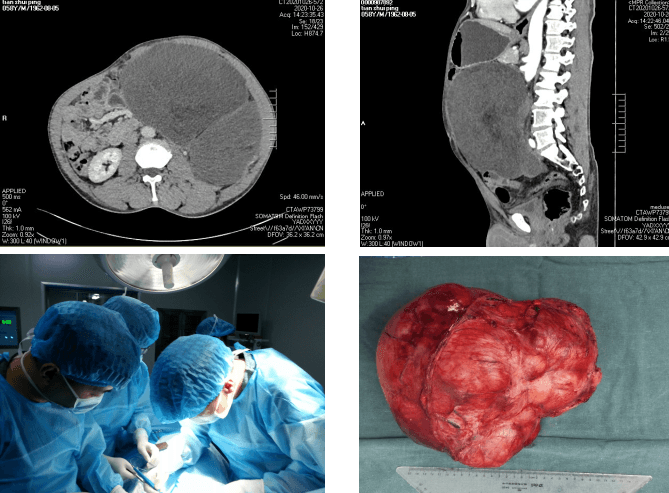

田某,男,50岁,因“腹胀6月余”入院。查体见肿瘤占据整个腹部,经影像学检查,显示腹部见一巨大软组织肿块影。苗主任对老人的身体进行仔细评估,术前检查完善后,科室反复讨论后,组织MDT多学科会诊决定实施手术切除,并制定了详细的手术方案及围手术期应急预案。2020年5月22日上午,由苗满园教授、李仁拴主治医师等组成的手术团队在全麻下为患者行“腹膜后巨大肿瘤切除术”。术中发现肿瘤位于腹膜后,约35cm×30cm×30cm,不规则型,实质性,占据左侧腹腔空间,将腹腔内肠管等推挤至腹腔右侧,左肾被挤压至右上腹,右侧输尿管扩张。术中仔细分离,保护好肠系膜血管、腹主动脉、胰腺、脾脏、结肠等重要器官,在手术室的密切配合下,手术历时3小时完成,切除肿瘤重达10kg。围手术期严格执行ERAS流程,给予早期恢复饮食、术后第一天即可下床活动、多模式镇痛等一系列治疗措施,患者恢复顺利,于术后10天治愈出院。术后病理提示腹膜后高分化脂肪肉瘤。

腹膜后肿瘤早期症状隐匿,常在生长至较大时出现症状被发现,但此时肿瘤常累及大血管、消化系统、泌尿生殖系统等重要脏器,腹膜后肿瘤手术平均出血约2000ml,止血困难,易导致出血死亡,手术切除难度极大。本次手术亮点:1. 术前多学科MDT、充分术前准备,将手术风险尽可能降至最低;2. 精湛的手术技巧帮助闯过手术关:术中精细解剖,避免损伤周围脏器,完整切除了腹膜后巨大肿瘤;3. 个体化精准治疗让患者最大程度获益。